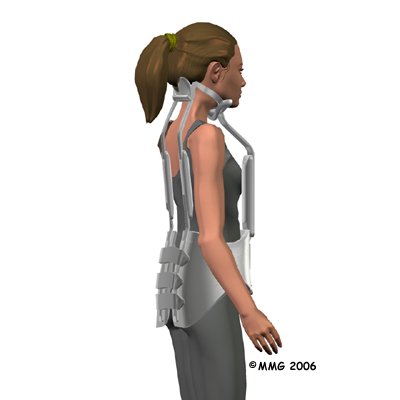

If your doctor is concerned that the curve will worsen, he or she may suggest bracing along with exercise. A brace is most effective when used before the skeleton matures at about age 14. Doctors commonly chose a Milwaukee brace, which is made of molded plastic that conforms to the waist and is designed to hold the shoulders back and gradually straighten the thoracic curve. On the back, two upright, padded bars line up along the sides of the spine. Pressure from the upright bars straightens the spine. The brace won't reverse the curve in a fully developed spine, nor is it helpful for rigid curves that angle more than 75 degrees.

Younger patients (under 15) generally wear the brace all the time including at night, although they usually remove the brace to shower. The doctor adjusts the brace regularly as the curve improves. When the thoracic curve has improved enough, the brace is worn part-time (eight to 12 hours per day) until the skeleton is done growing, which is typically around age 14 or 15.

Sometimes adults obtain partial correction of the kyphosis and pain relief with bracing even though they have reached full bone growth. Bracing for pain relief in adults is also considered when surgery is not an option.